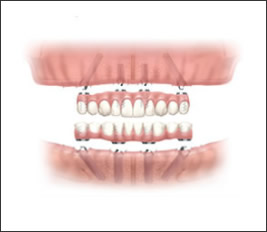

STEP4:最終ブリッジの取り付け

インプラントの埋入から約6ケ月後に、強度が強く美しい仕上がりの最終ブリッジと交換します。